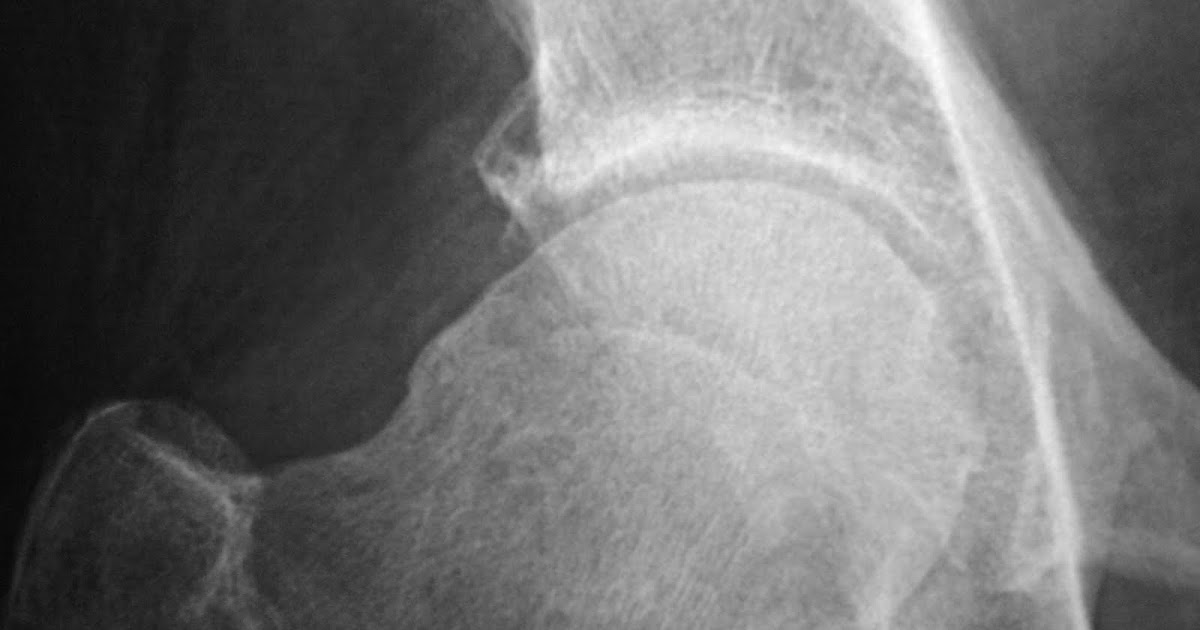

Pistol grip deformity seen on an anteroposterior xray of the left hip... Download Scientific What Is Pistol Grip Deformity Femoroacetabular impingement (fai) is the abnormal contact between the femur and acetabulum which may lead to labral damage, various degrees of chondral injury and. The overgrown or misshapen bone contacts the cartilage that lines the hip socket, and can cause it to peel away from the bone in the socket. Pistol grip deformity (pgd) may be the main factor in. What Is Pistol Grip Deformity.

Pistol grip deformity seen on an anteroposterior xray of the left hip... Download Scientific What Is Pistol Grip Deformity The overgrown or misshapen bone contacts the cartilage that lines the hip. The overgrown or misshapen bone contacts the cartilage that. Femoroacetabular impingement (fai) is the abnormal contact between the femur and acetabulum which may lead to labral damage, various degrees of chondral injury and. Pistol grip deformity (pgd) may be the main factor in femoroacetabular impingement development. The overgrown. What Is Pistol Grip Deformity.